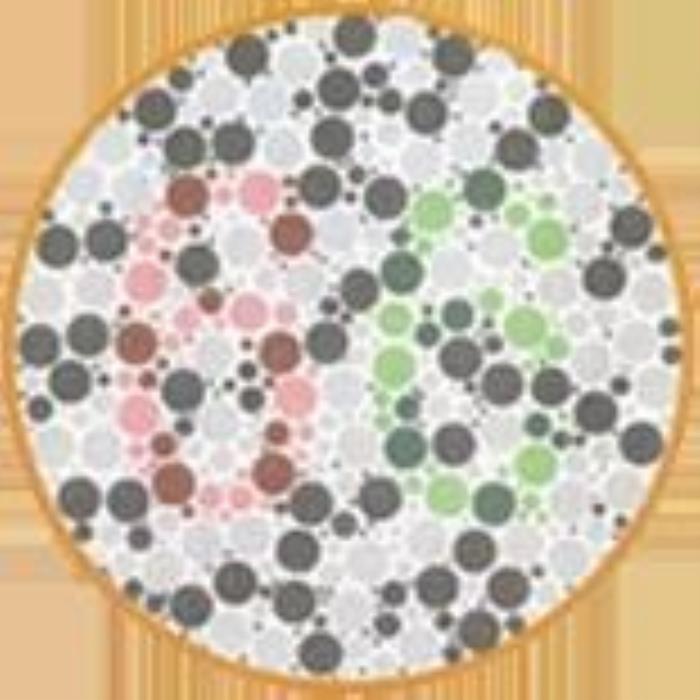

(正常 绿色盲 红色盲 蓝黄色盲)

(正常 绿色盲 红色盲 蓝黄色盲)

根据不同类型的色盲,以及色盲的严重程度,患者多少是能看到一些颜色的,或者说只是有些颜色看起来跟常人不同,但并不等于是“黑白”的世界。